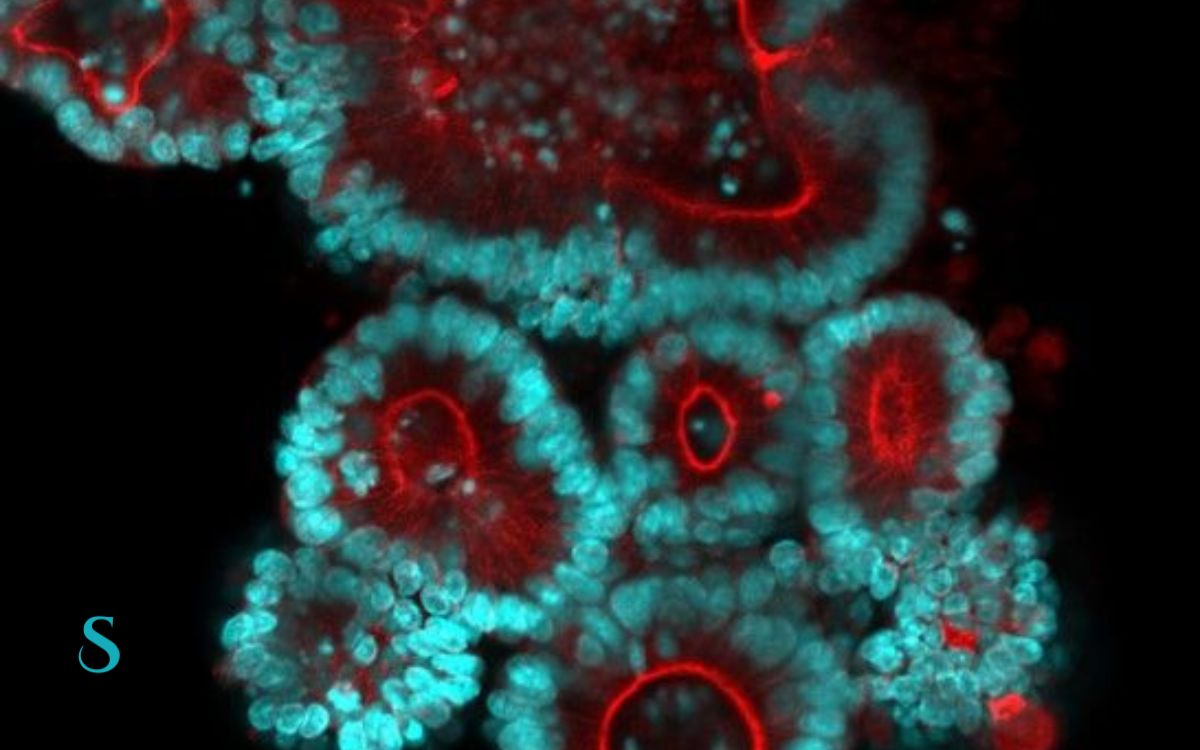

Continue readingi3S desenvolve organoides para terapias personalizadas em tumores pediátricos

Investigadores do i3S avançam na medicina de precisão ao criar organoides de tumores cerebrais pediátricos a partir de material cirúrgico de doentes pediátricos.